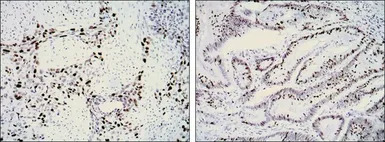

IHC-P analysis of lung cancer (left) and rectal cancer (right) using GTX82777 Ki67 antibody [8D5].